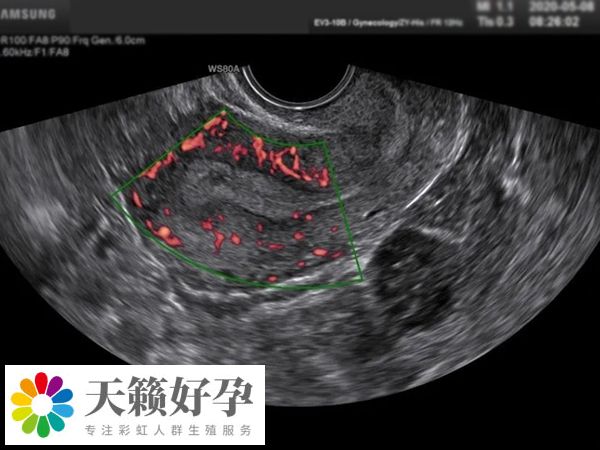

此外,睾丸超聲還可以幫助醫生評估睾丸中的血管和血流情況,這對於(yu) 評估睾丸功能是否正常非常重要。在一些情況下,如果懷疑有睾丸功能障礙,醫生可能會(hui) 建議進行進一步的檢查。